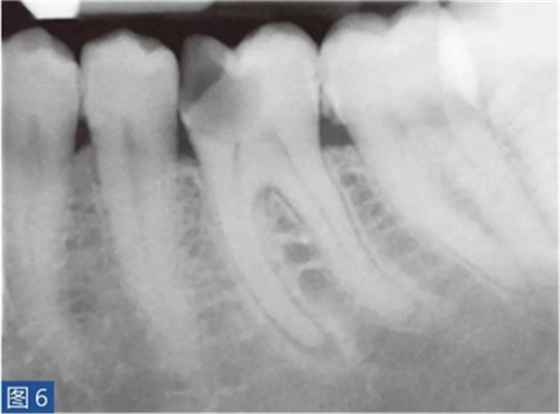

致密性骨炎(圖6 和7)是AAP 的一個(gè)變種。造成致密性骨炎的原因是,根尖周組織受到長期的持續(xù)性刺激。臨床檢查時(shí),對(duì)敏感測(cè)試、叩診和觸診可能有反應(yīng),也可能無反應(yīng)。放射學(xué)檢查,牙齒的根尖周圍存在彌漫性的致密阻射影像。

圖6:36 牙齒CO。術(shù)前X 線片?;颊咭蜓例X36 充填物脫落而前來就診。X 線片顯示遠(yuǎn)中根的根尖區(qū)有白色阻射影像。近中根的根尖區(qū)顯示在白色阻射區(qū)內(nèi)有透射影像。